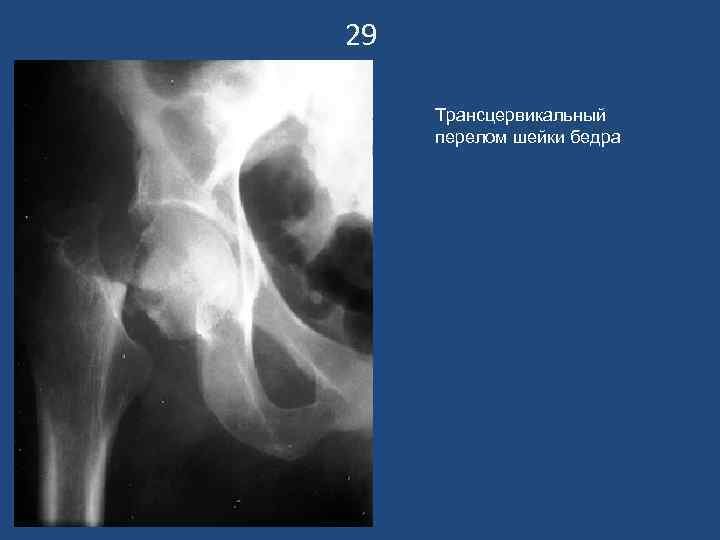

29 Трансцервикальный перелом шейки бедра